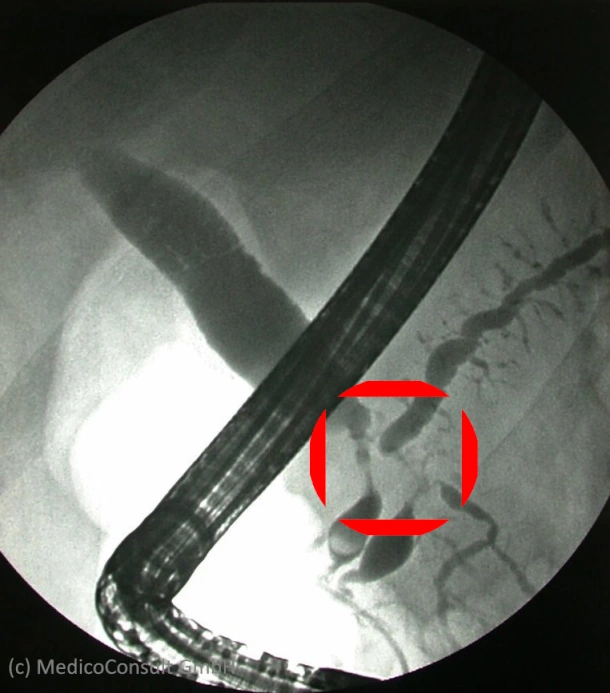

Differenzialdiagnostisch kommt bei einer schmerzlosen Gelbsucht (Ikterus) mit gestauten Gallenwegen, die sonographisch bis zum Pankreas verfolgbar sind, auch ein Papillentumor oder ein distales cholangioläres Karzinom (Krebs im Gallengang) in Betracht. Die Klärung bringen weitere bildgebende Verfahren, inkl. einer MRCP. Eine ERCP wird dann indiziert sein, wenn es um eine Ableitung der gestauten Galle in den Zwölffingerdarm geht.

Die Behandlung richtet sich nach der Ursache. Es kommen medikamentöse, chemotherapeutische und operative Maßnahmen infrage. Zur palliativen Behandlung einer obstruktiven Cholestase (durch Gallengangsverschluss) kann im Rahmen einer interventionellen ERC ein Stent (Plastik- oder Metallgitterröhrchen) in den Gallengang implantiert werden, der das Hindernis überbrückt.